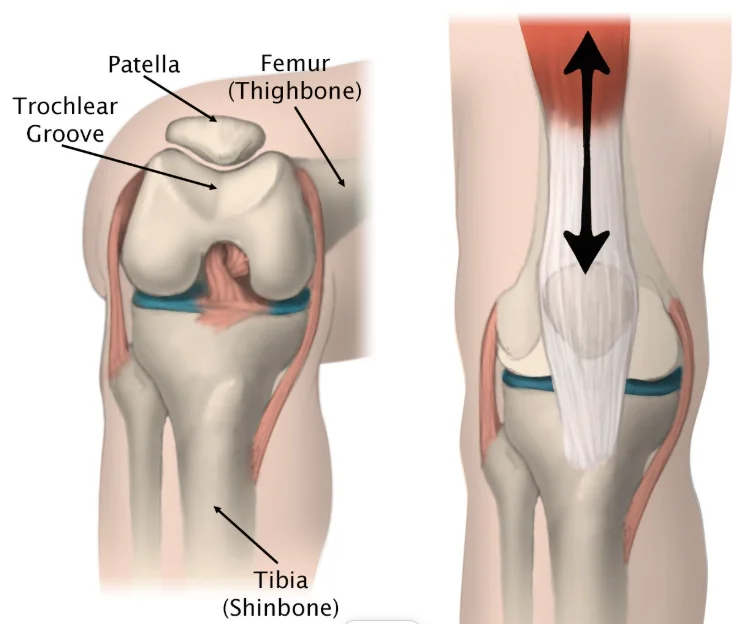

A patella dislocation occurs when your kneecap (patella) slides out of the groove at your knee joint. Knee joint is formed by three bones: thighbone (femur), shinbone (tibia) and patella in the middle. Normally, when you bend and straighten your leg, your kneecap slides up and down inside a vertical groove (the trochlear groove) between the bottom end of your femur and the upper end of your tibia. A group of tendons and ligaments stabilize patella within the groove, prevents its dislocation.

When the patella dislocates, it’s forced outside of the trochlear groove and can no longer move up and down. This locks your knee and pulls the ligaments out of place, often tearing them. Most frequently, patella dislocates laterally (outer side of knee joint).